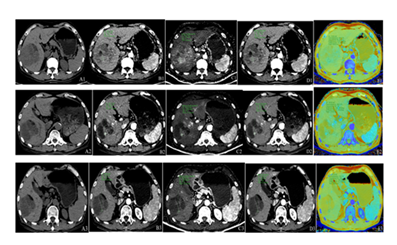

Figure 3: Male patient, 67 years old, with giant hepatocellular carcinoma. Panels A1–A3 represent unenhanced CT images; B1–B3, conventional arterial-phase images; C1–C3, iodine density maps in the arterial phase; D1–D3, spectral images at 40 keV in the arterial phase; and E1–E3, effective atomic number maps in the arterial phase. Panels A1–E1 display pre-radiotherapy imaging findings: unenhanced CT reveals a large, heterogeneous hypodense mass in the right hepatic lobe; arterial-phase imaging shows marked enhancement; iodine density mapping demonstrates a region of high iodine uptake; low-energy spectral imaging (40 keV) clearly delineates the lesion with well-defined margins; and atomic number mapping reveals predominantly light green signal intensity within the tumor. Panels A2–E2 depict imaging findings after the first cycle of radiotherapy: compared to baseline, there is a reduction in lesion size, density, enhancement extent, iodine uptake area, and solid components, with concomitant expansion of cystic necrotic regions. Panels A3–E3 illustrate post-second-cycle radiotherapy imaging: further reduction in tumor size and enhancement range is observed, iodine uptake is nearly absent, solid components are minimal, and the necrotic component has expanded.